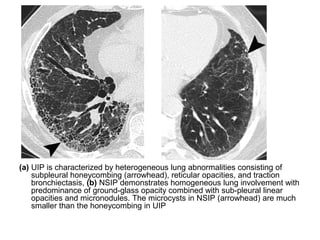

(a) UIP is characterized by heterogeneous lung abnormalities consisting of

subpleural honeycombing (arrowhead), reticular opacities, and traction

bronchiectasis, (b) NSIP demonstrates homogeneous lung involvement with

predominance of ground-glass opacity combined with sub-pleural linear

opacities and micronodules. The microcysts in NSIP (arrowhead) are much

smaller than the honeycombing in UIP